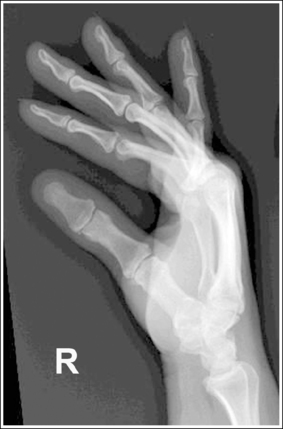

Hand: Posteroanterior Projection

See Figure 4-22 and Box 4-8.

The digits and metacarpals demonstrate a PA projection. The soft tissue outlines of the second through fifth phalanges are uniform, the distance between the metacarpal heads is equal, and the same midshaft concavity is demonstrated on both sides of the phalanges and metacarpals of the second through fifth digits.

• A PA projection of the hand is obtained when the patient fully extends the hand and rests the palmar surface flat against the IR (Figure 4-23).

• PA versus external oblique hand position. If the hand is not fully extended but is slightly flexed, it often relaxes into an external PA oblique projection when it is resting against the IR. A PA oblique hand projection is signified by slight superimposition of the third through fifth metacarpal heads and unequal soft tissue thickness and midshaft concavity on the sides of the phalanges. The metacarpals also show unequal midshaft concavity and spacing (see Image 20). Abducting the patient's arm and placing the forearm and humerus on the same horizontal plane, with the elbow flexed 90 degrees, assists in preventing an externally rotated PA oblique projection and will best demonstrate the wrist. This is important if a wrist condition is causing radiation hand pain. When the patient has been positioned in this manner, the ulnar styloid appears in profile on the image. Internal rotation of the hand is seldom a problem, because the thumb prevents this movement.

Image 20

No soft tissue overlap of adjacent digits is present.

The IP, MP, and CM joints are visible as open spaces, and the phalanges and metacarpals are not foreshortened. The thumb is demonstrated in a 45-degree PA oblique projection.

• When the hand and fingers are fully extended and a perpendicular central ray is centered to the third MP joint space, the IP, MP, and CM joints are demonstrated as open spaces and the phalanges and metacarpals are seen without foreshortening on the PA hand projection.

• Flexion of the hand causes poor alignment of the phalanges, metacarpals, and IP and CM joint spaces with the IR and central ray, resulting in closed joint spaces and foreshortening of the phalanges and metacarpals (see Image 21). The position of the first digit also changes when the image is taken with the hand flexed, because flexion rotates the first digit into a lateral projection.

Image 21

The third MP joint is at the center of the exposure field. The distal, middle, and proximal phalanges, the metacarpals, the carpals, and approximately 1 inch (2.5 cm) of the distal radius and ulna are included within the collimated field.

• Center a perpendicular central ray to the third MP joint to place it in the center of the collimated light field. This MP joint is situated just slightly distal to the head of the third metacarpal. Once the central ray is centered, open the longitudinal collimation to include the distal phalanx and 1 inch (2.5 cm) of the distal forearm. Transversely collimate to within 0.5 inch (1.25 cm) of the first and fifth finger's skin line.

• Either half of a 10- × 12-inch (24- × 30-cm) detailed screen-film IR placed crosswise or a single 8- × 10-inch (18- × 24-cm) digital IR placed lengthwise should be adequate to include all the required anatomic structures.

• Pediatric bone age assessment. A bone age image is obtained to assess the skeletal versus the chronologic age of a child. Because bones develop in an orderly pattern, skeletal age may be assessed from infancy through adolescence. Illness, metabolic or endocrine dysfunction, and taking certain types of medications and therapies are all reasons why a pediatric patient's skeletal and chronologic age may not correspond. A left PA hand and wrist projection is typically the image of choice because bony developmental changes are readily visible and easily evaluated. For skeletal age to be evaluated, the phalanges, metacarpals, carpals, and distal radius and ulna must be included in their entirety (see Figure 1-130).

The hand was externally rotated, as indicated by the superimposition of the third and fourth metacarpal heads, the unequal midshaft concavity on either side of the phalanges and metacarpals, and the uneven spacing of the metacarpal heads. The tip of the second and third fingers has been collimated off, and less than 1 inch (2.5 cm) of the distal radius and ulna is included.

Internally rotate the hand until the palm and fingers are placed flat against the IR, and open the longitudinally collimated field to include the second and third fingertips and 1 inch (2.5 cm) of the distal radius and ulna.

See Figure 4-24 and Box 4-9.